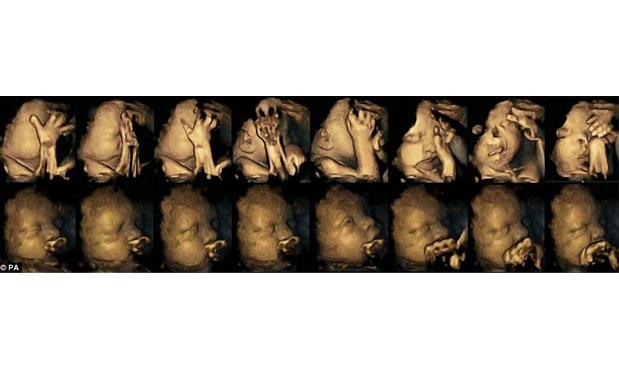

Todo mundo sabe que não se deve fumar na gravidez. Mas talvez os efeitos do cigarro nunca tenham ficado tão claros antes dessa pesquisa, feita pela Universidade de Durham, na Inglaterra: os bebês das mães fumantes colocavam as mãos no rosto e na boca com muito mais frequência do que os bebês de mães não fumantes. Isso pode significar um atraso no desenvolvimento, já que quanto mais velhos e desenvolvidos estão, menos os bebês fazem esse movimento. Esses ultrassons mostram o quanto o sistema nervoso desses bebês está atrasado.

Para o estudo, foram analisadas 20 gestantes, das quais 4 fumavam em média 14 cigarros por dia. A Dra Nadja Reissland, que conduziu o estudo, disse que ainda é necessário uma pesquisa maior para investigar efeitos específicos, inclusive a ligação entre stress materno e tabagismo.